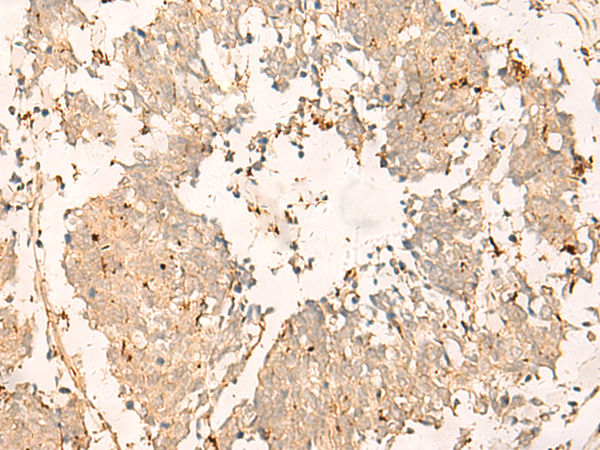

分类: 科研抗体货号: P09961别名: TGC1; TSGA3; SPGFX2应用: IHC反应种属: Human